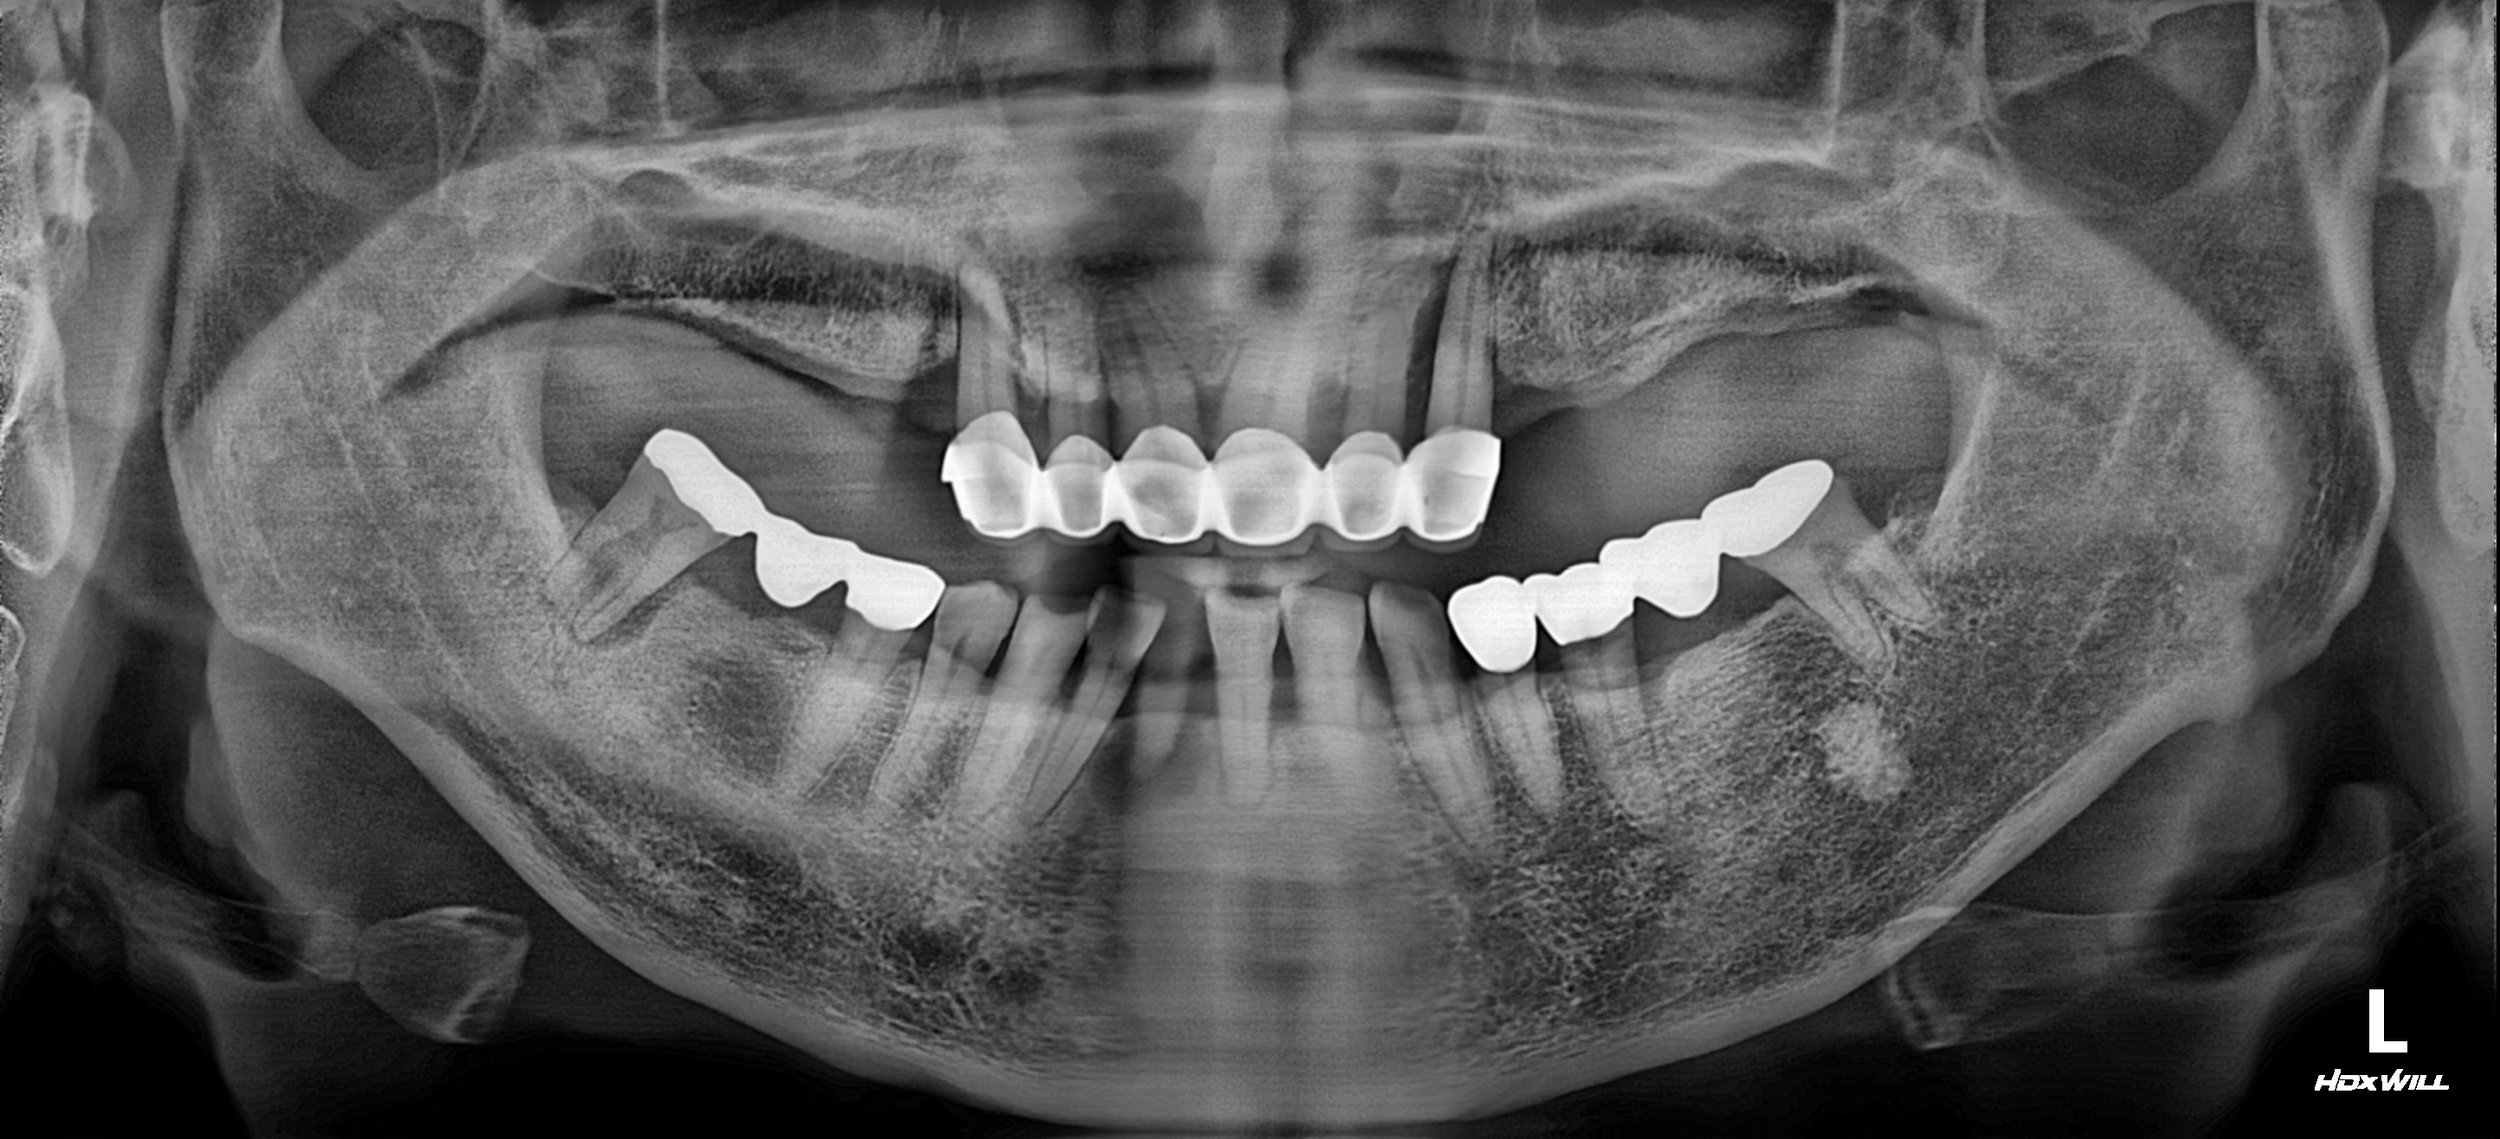

OPG - BEFORE

A male patient in his 60s presented with a severely compromised oral condition. Having relied on ill-fitting and unusable partial dentures for a long period, his remaining dentition had deteriorated significantly. Key clinical findings included:

• Failing Anterior Bridge: The existing maxillary anterior bridge exhibited significant mobility due to the poor condition of the abutment teeth.

• Severe Mandibular Crowding: Due to long-term posterior tooth loss and lack of space, the mandibular anterior teeth showed significant lingual displacement (lingual position).

• Occlusal Collapse: The loss of posterior support led to a collapse in the vertical dimension, making functional chewing impossible.

• Abutment Degradation: Most remaining teeth that previously served as denture or bridge supports were no longer restorable.